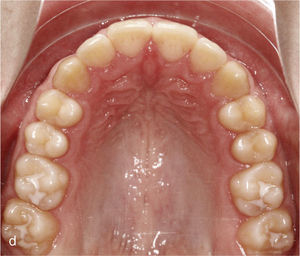

La expansión transversal constituye una alternativa a la reducción de esmalte interproximal para corregir apiñamientos y para dotar a las arcadas de un aspecto armonioso. La figura 4a muestra un maxilar estrecho en el plano transversal y dientes muy rotados y apiñados en el sector anterior. En este caso fue posible lograr una arcada armoniosa utilizando anclajes en los dientes 14, 13, 23 y 24 con ataches verticales, expansión transversal, protrusión del diente 21 y reducción del esmalte interproximal (fig. 4b).

Sector anterosuperior con dientes 11 y 21 en mesioversión y triángulo negro interdental (a). Se colocaron ataches rectangulares verticales en los dientes 11 y 21 y en los anteriores adyacentes. Resultado del tratamiento después de enderezar los dientes 11 y 21 y de cerrar el triángulo negro (b).